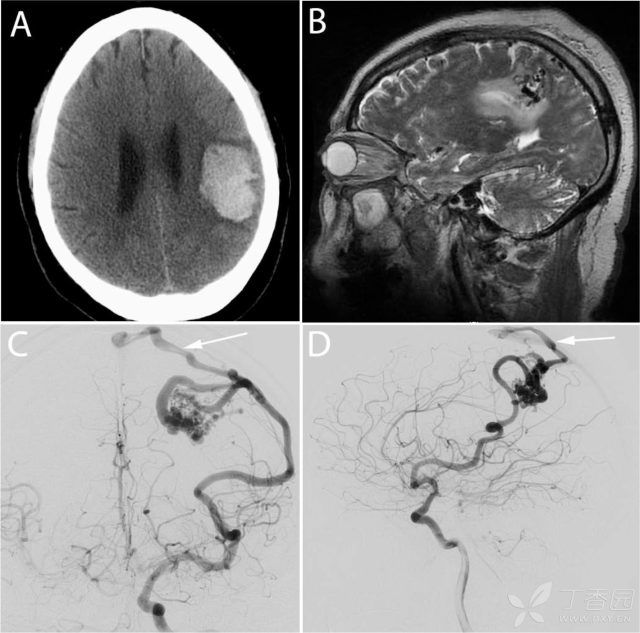

我看了片子,脑出血是肯定的,立即心电监护和吸氧,按照脑出血治疗,绝对卧床。

脑出血俗称脑溢血,简单的理解就是脑子里面出血了。脑出血虽然可因外伤引起,但在急性脑血管病的分类中,一般指的是非外伤性的,又称原发性或自发性脑出血。

脑出血的病情严重程度主要取决于出血位置和出血量,而且脑出血一旦发生通常只能就地救治,所以有些患者没法得到有效救治,致残率和致死率都非常高。